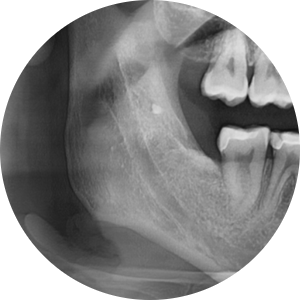

그렇다면 상일동 치과 사랑니 케이스를 확인해볼까요?

240827